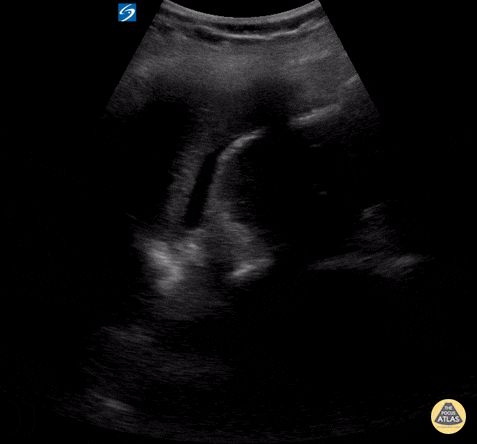

Pediatric patient with blunt abdominal trauma and free fluid in LUQ. Contributor: Peter Gutierrez, MD FAAP FACEP; Children's Healthcare of Atlanta; @pocuspete